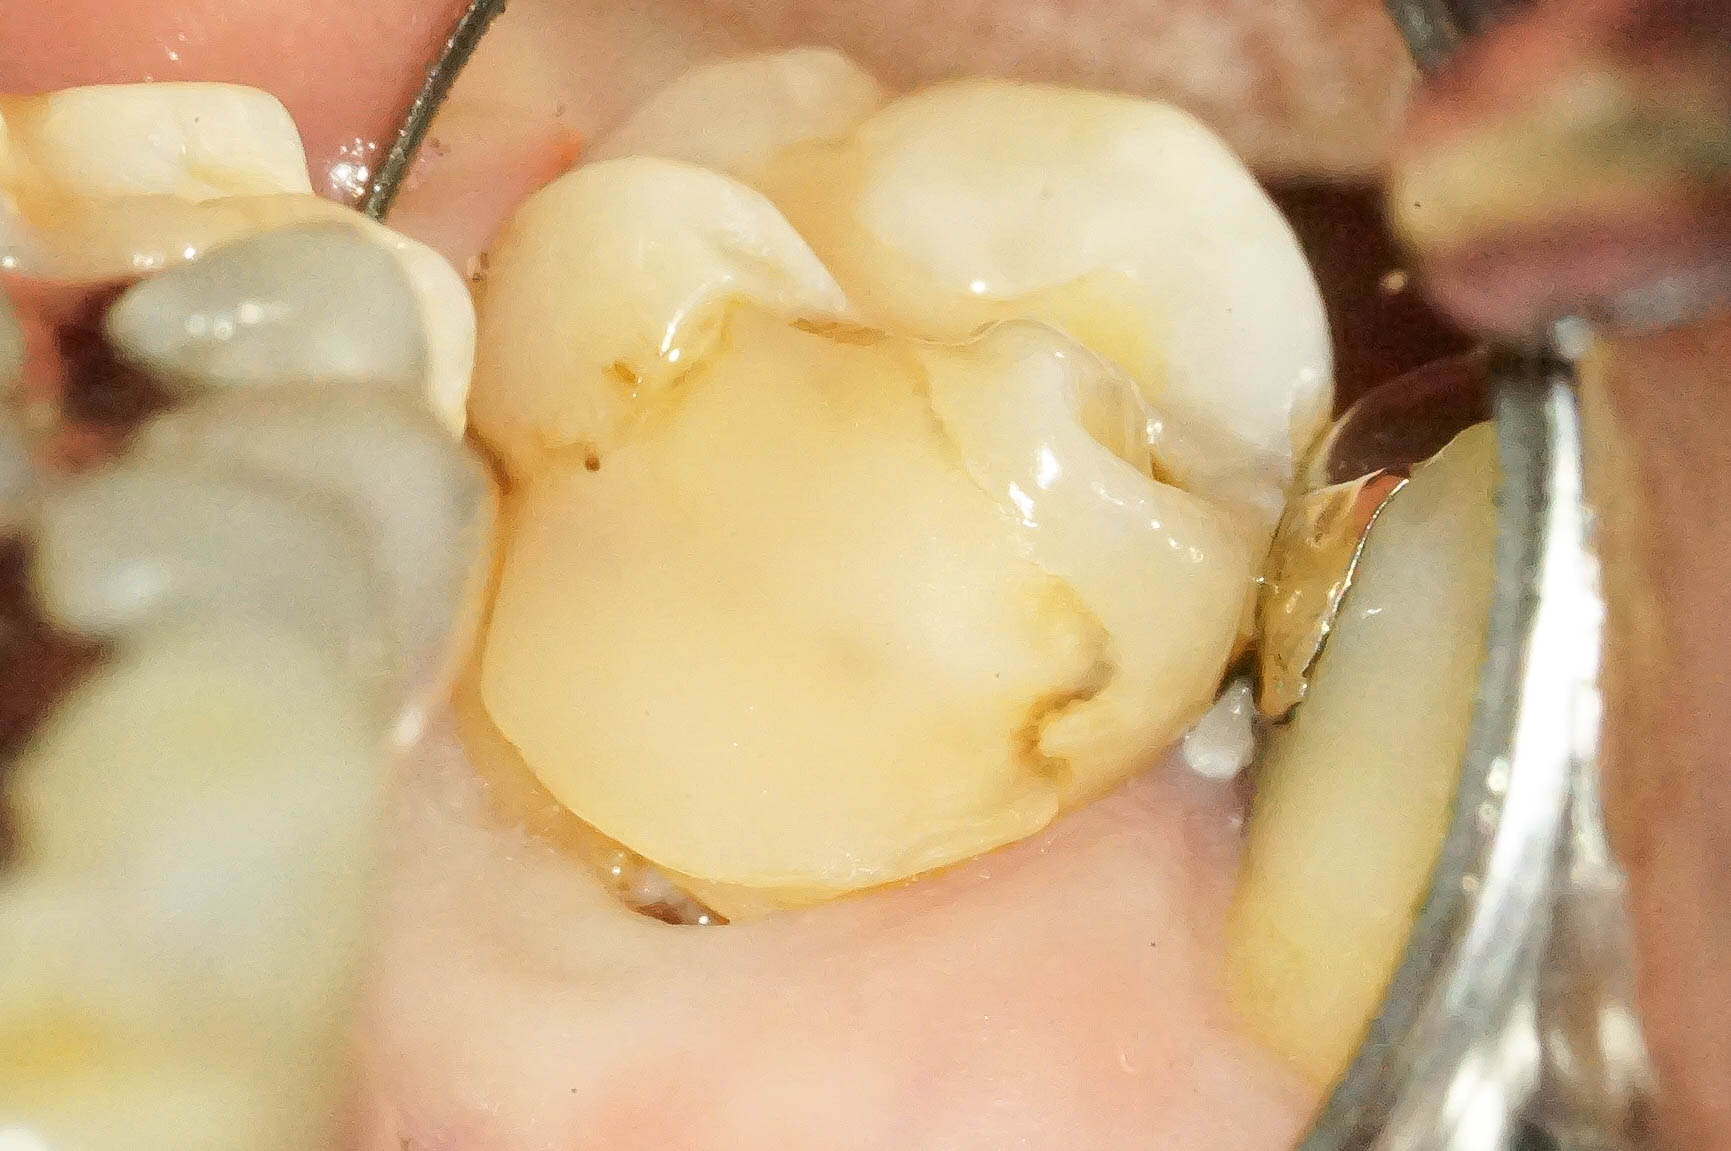

歯肉縁下ダイレクトボンディングを行った症例治療方法02

拡大して見てみると歯と歯肉の境目に齲蝕を認めます。

いわゆる普通の、保険治療でよく見かけるコンポジットレジンのその後 ですね。

治療直後はなにもトラブルが起きていませんが、数年後にトラブルが起き始める典型的な例です。